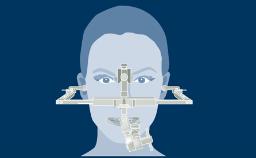

There are various risk factors that may affect the success and survival rates. A clinician planning an implant therapy needs to know the risk factors that contribute to the different types of complications that can occur after implant treatment.

- identify the different types of complications that may be involved in implant therapy

- identify the risk factors for these complications